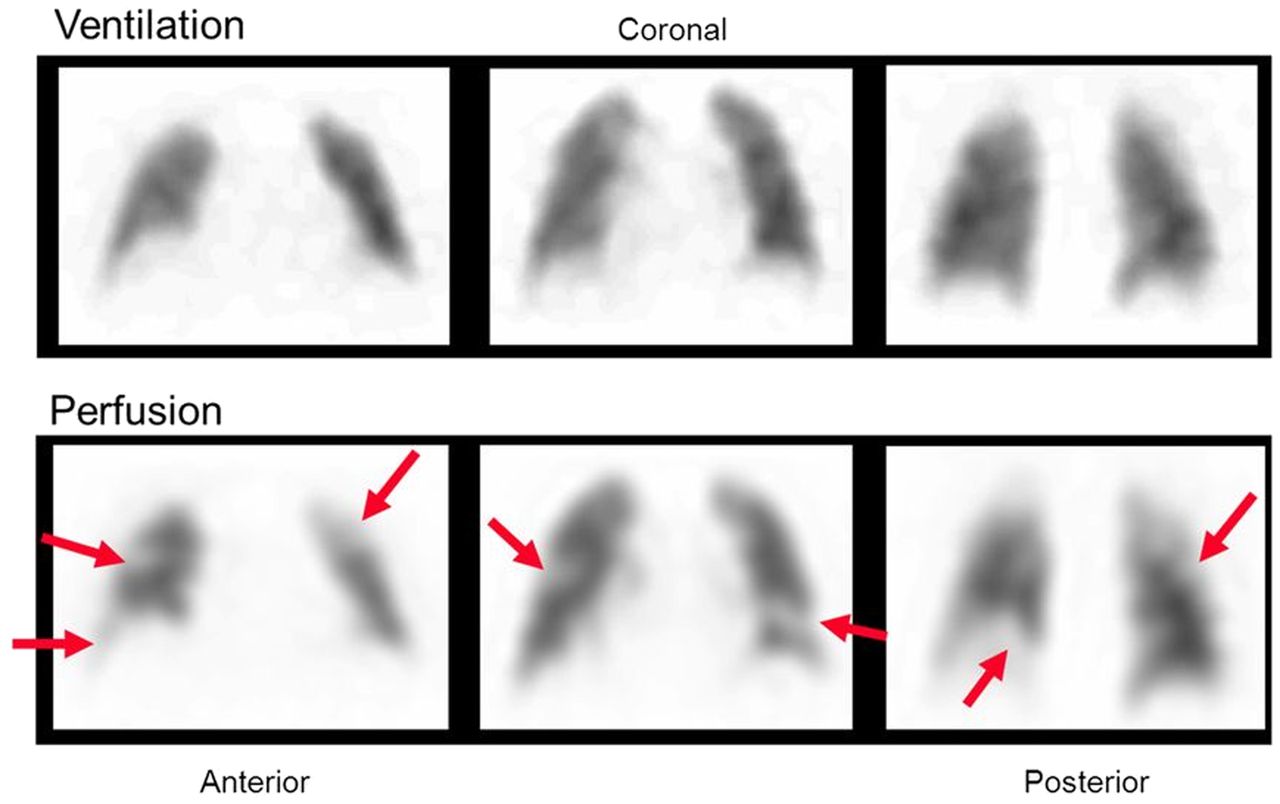

Lung Ventilation Perfusion (V/Q) Scan indications Nuc Med

Indication: Pulmonary Embolism

Lung Ventilation Perfusion scan Nuc Med vs CTPA

Lung (V/Q) Advantages:

Contrast allergy

Less ionising for pregnant patients

Can image those with renal impairments

Pharmaceuticals used in Lung (V/Q) scans

Ventilation= 99mTc Technegas

Perfusion= 99mTc MAA

PE Appearance in Lung (V/Q) scan

Normal ventilation, perfusion defect (mismatch)

Poor image quality causes for Lung V/Q scan

COPD= poor ventilation distribution